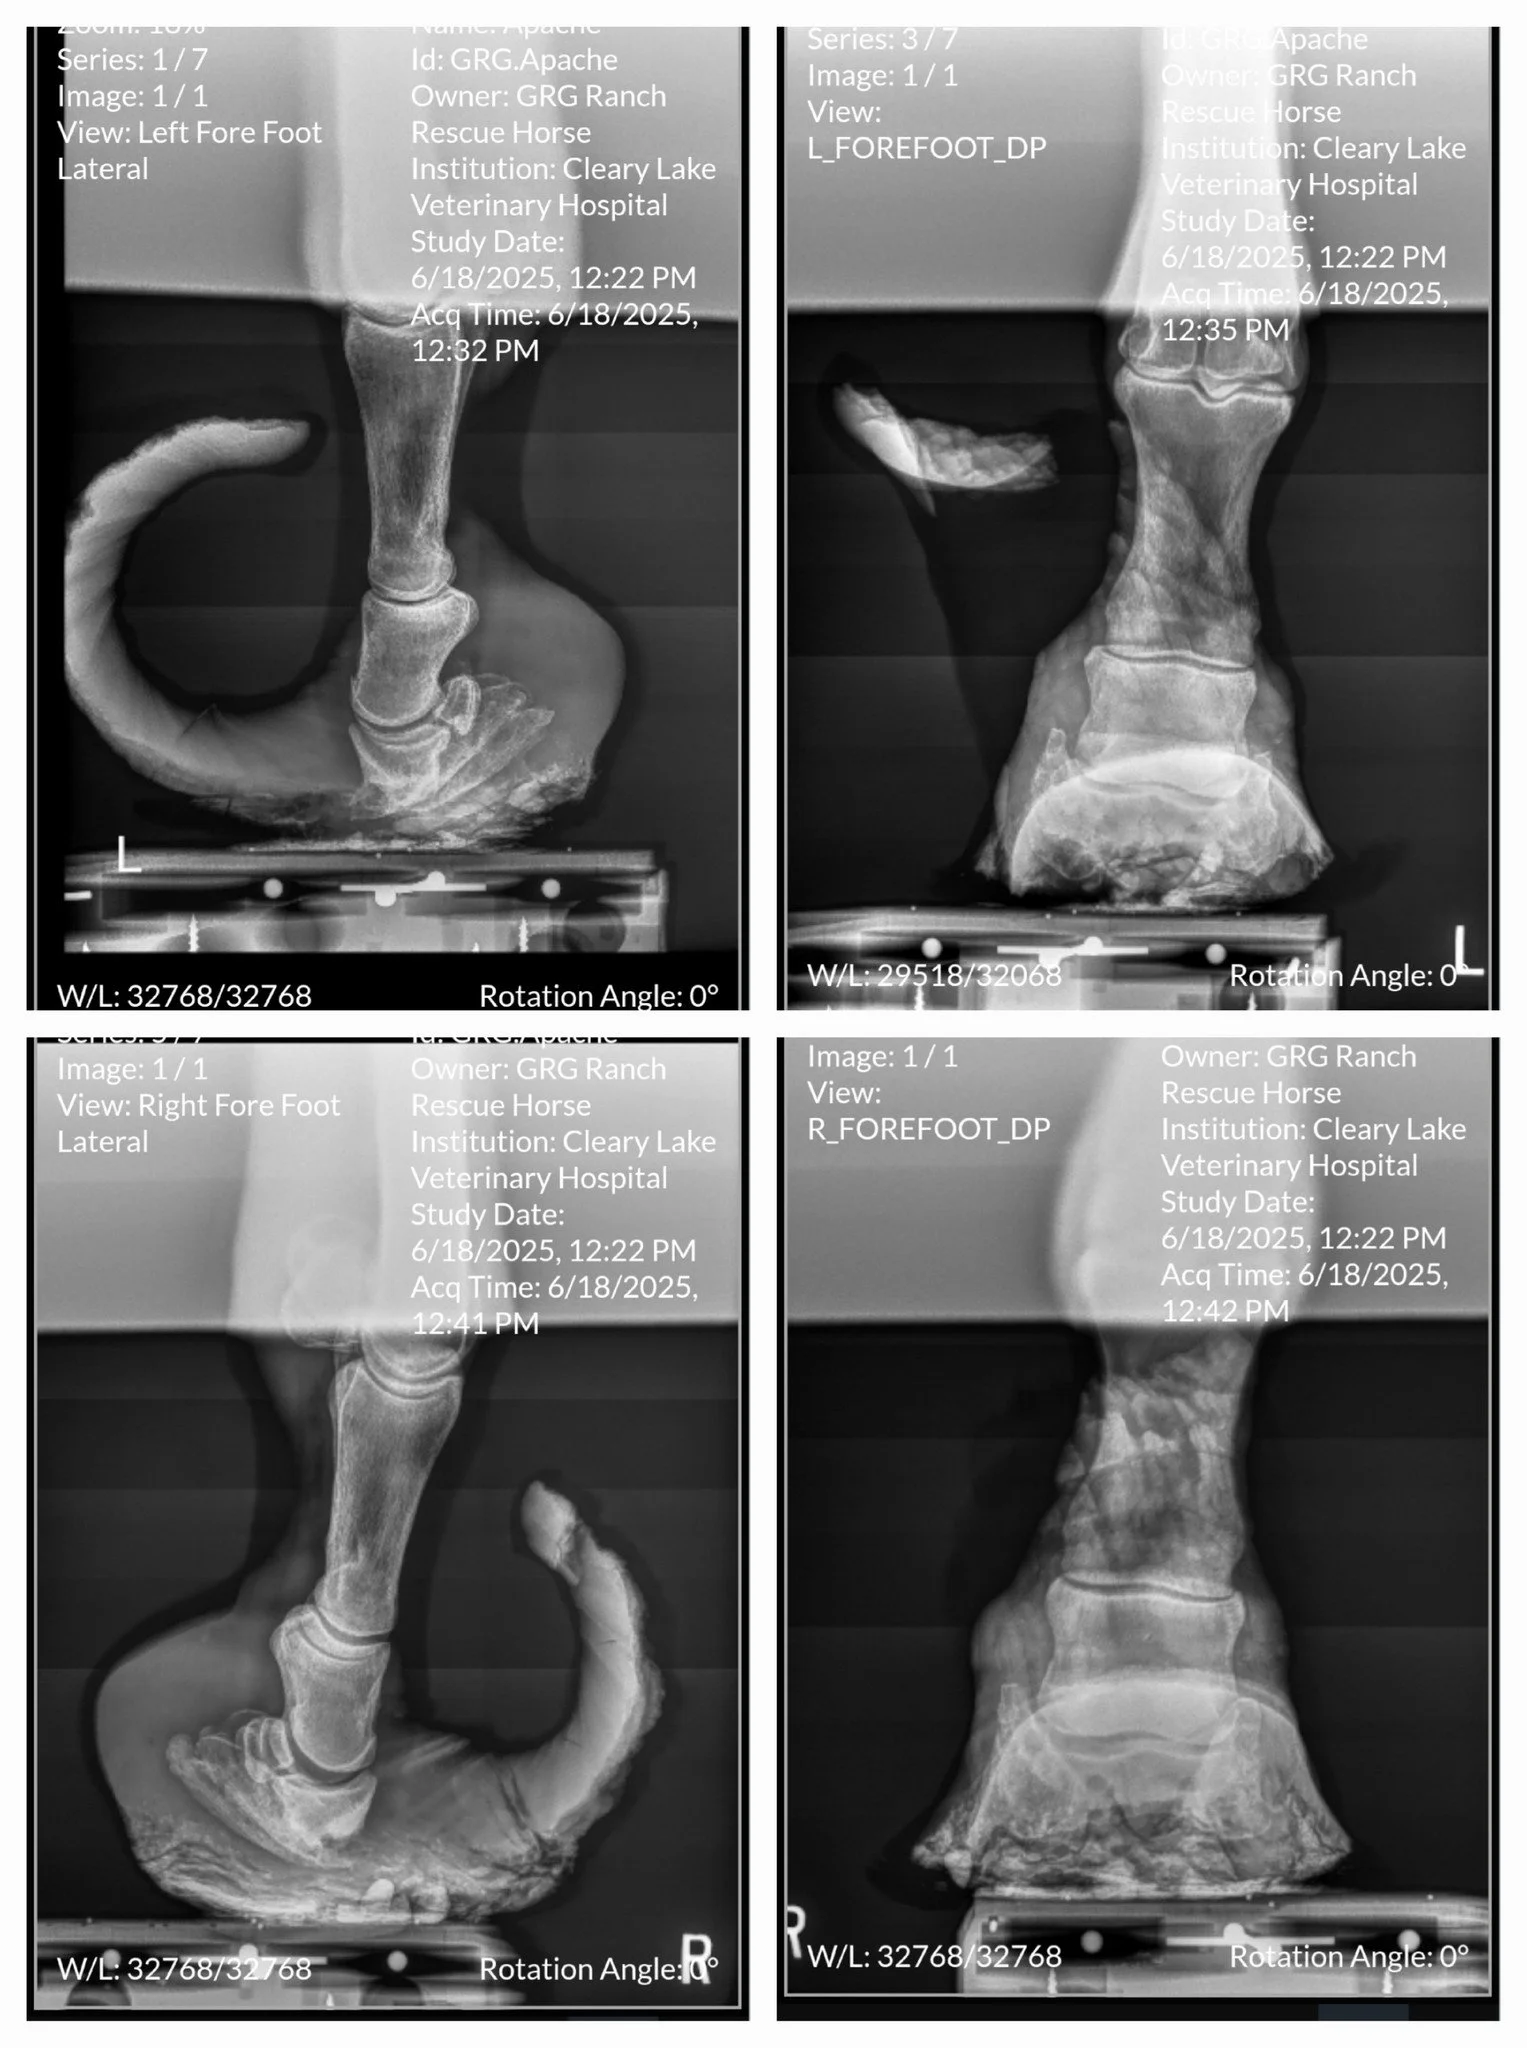

But when you look down, you see it. Hooves so overgrown they haven’t been properly addressed in years.

Overgrown hooves aren’t cosmetic.

They change the mechanics of the entire body, affecting bones, joints, tendons, circulation, posture, and comfort.

Pain doesn’t always present as collapse or starvation. Sometimes it shows up as compensation, stiffness, or quiet suffering.

• You can’t see inside a hoof without X-rays.